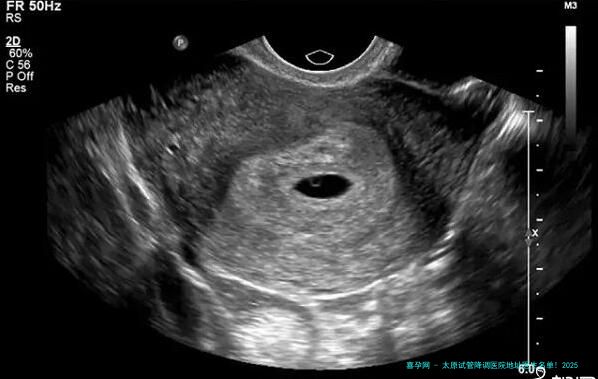

问题:降调到底是何物?为什么它如此关键?

答案:降调是通过药物抑制垂体功能,让卵泡立在同一起跑网络上,避免提前排卵!降调成功与否直接决意促排成果,太原医院降调方案个性化程度高达90!